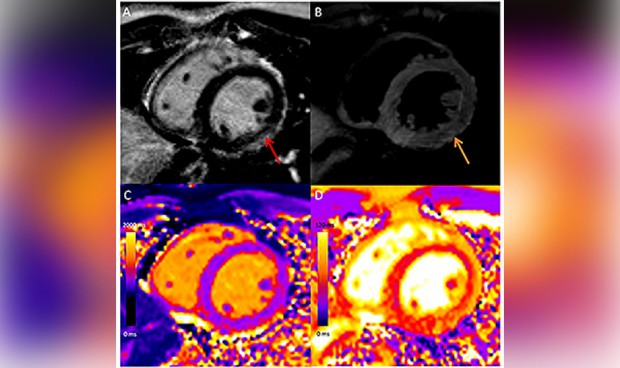

En cuanto a los hallazgos de la resonancia magnética en la miocarditis asociada a la vacuna mostraron un realce tardío de gadolinio en el 81 por ciento de los casos y una disfunción ventricular izquierda en el 29 por ciento.

“La resonancia magnética cardíaca mostró que en comparación con otras causas de miocarditis los pacientes con miocarditis asociada a la vacuna tenían menos deterioro funcional y anomalías miocárdicas menos extensas. Mientras que los pacientes con miocarditis tras superar el covid y otras miocarditis tenían una mayor prevalencia de anomalías que involucraban el tabique interventricular y peor lesión miocárdica medida por mapeo T1”, concluyen los investigadores.